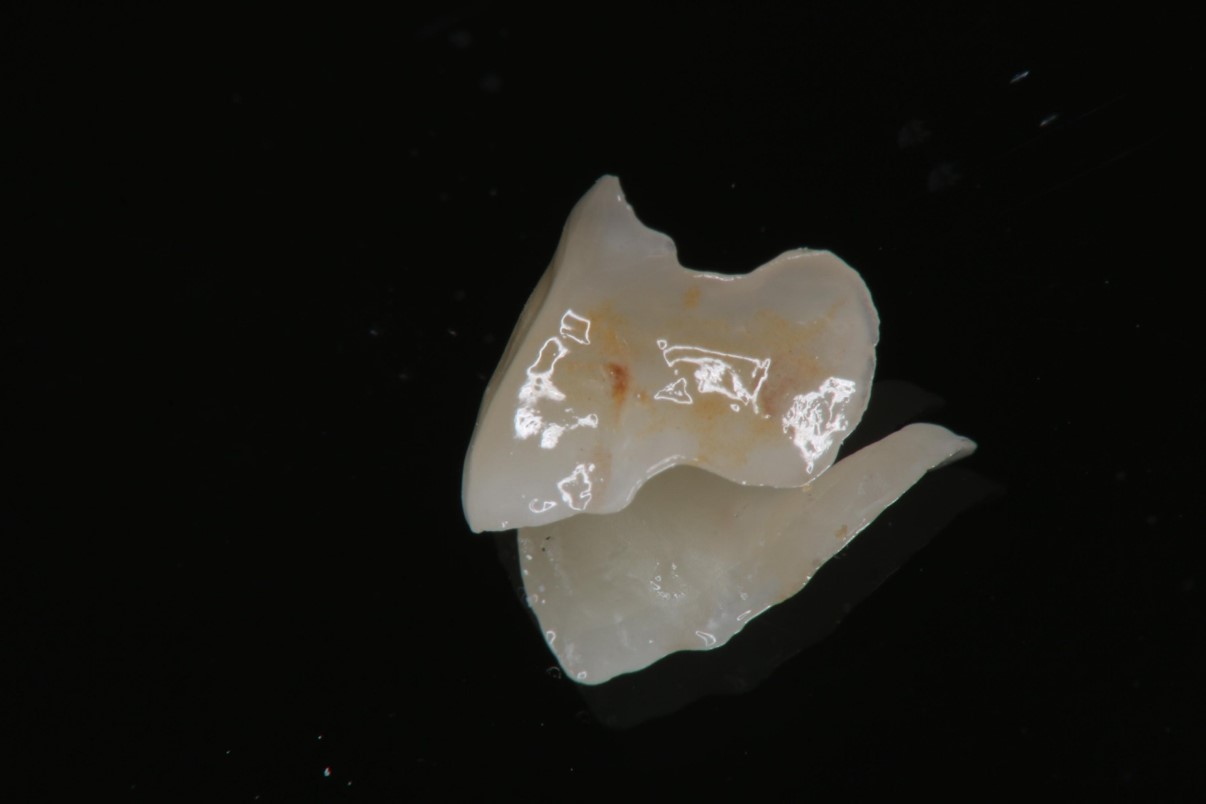

大臼齒的陶瓷崁體